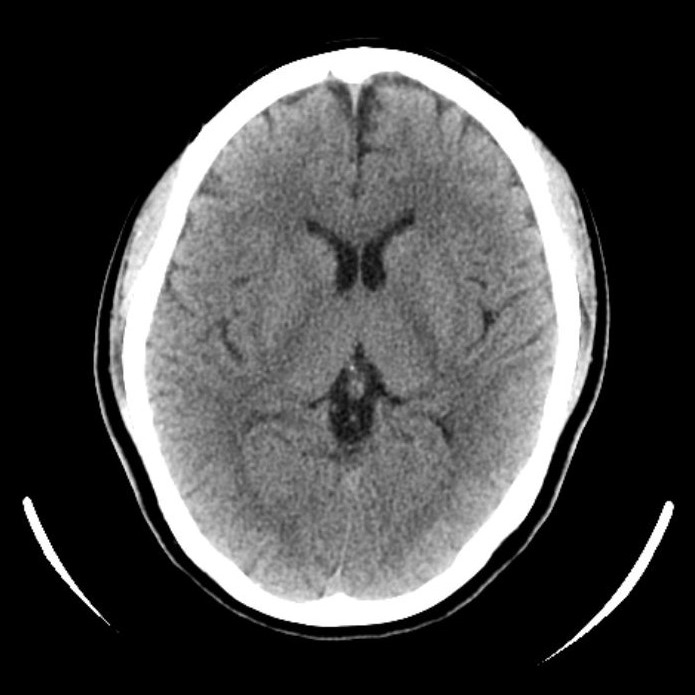

CT室:Aquilion ONE (Canon)・Revolution EVO (GE)

CTとは、X線という放射線を使用して人体の輪切り画像を撮る装置です。その画像を使用して、さまざまな方向の断面像や3Dの画像を再構成をすることもあります。

当院には320列と64列のCTがあります。

■320列CT (Aquilion One)

頭と心臓の検査